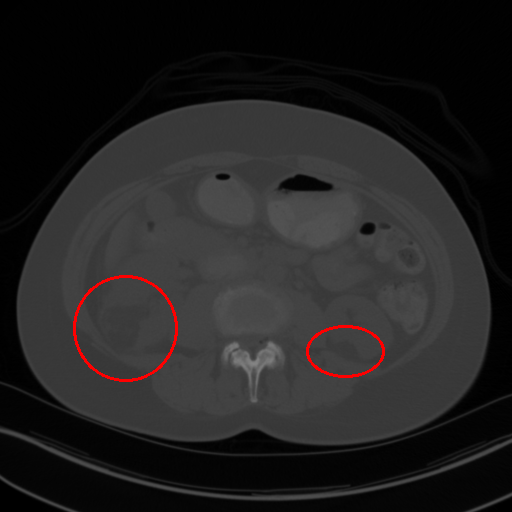

(b) [50, 449]

Figure 1: CT images under different window level and window width. (a) is the image used in 3DCE. (b),(c),(d) are the multi-view images used in our MVP-Net.

To accommodate for network input, previous studies [5, 6] use a significantly wide window222Windowing, also known as gray-level mapping, is used to change the appearance of the picture to highlight particular structures. to compress CT’s 12bit Hounsfield Uint (HU). However, this would severely deteriorate the visibility of lesions as a result of degenerated image contrast, as shown in Fig.1(a). In the clinical practice, fusing information from multiple windows are effective in improving the accuracy of detecting subtle lesions and reducing false positives (FPs). During visual inspection of the CT images, radiologists would combine complex information of different inner structures and tissues from multiple reconstructions under different window widths and window levels to locate possible lesions. To imitate this process, we propose to extract prominent features from three frequently examined window widths and window levels and capture complementary information across different windows with an attention based feature aggregation module.

The multi-view input for the MVP-Net is composed of multiple reconstructions under different window widths and window levels. Specifically, we adopt k-means algorithm to cluster the recommended windows (labeled by radiologists) in the DeepLesion dataset and obtain three most frequently inspected windows, whose window levels and window widths are [50,449]50449[50,449], [505,1980]5051980[-505,1980] and [446,1960]4461960[446,1960] respectively. As shown in Fig.1, these clustered windows approximately correspond to the soft-tissue window, lung window, and the union of bone, brain, and mediastinal windows respectively.

We also perform a case study to analyze the importance of multi-view modeling. As shown in Fig. 3, the model indeed benefits from the multi-view modeling: the lesions that are originally indistinguishable in the view of 3DCE due to the wide window range and lack of contrast, now becomes distinguishable under the view of appropriate windows. Thus our model presents better identification and localization performance.